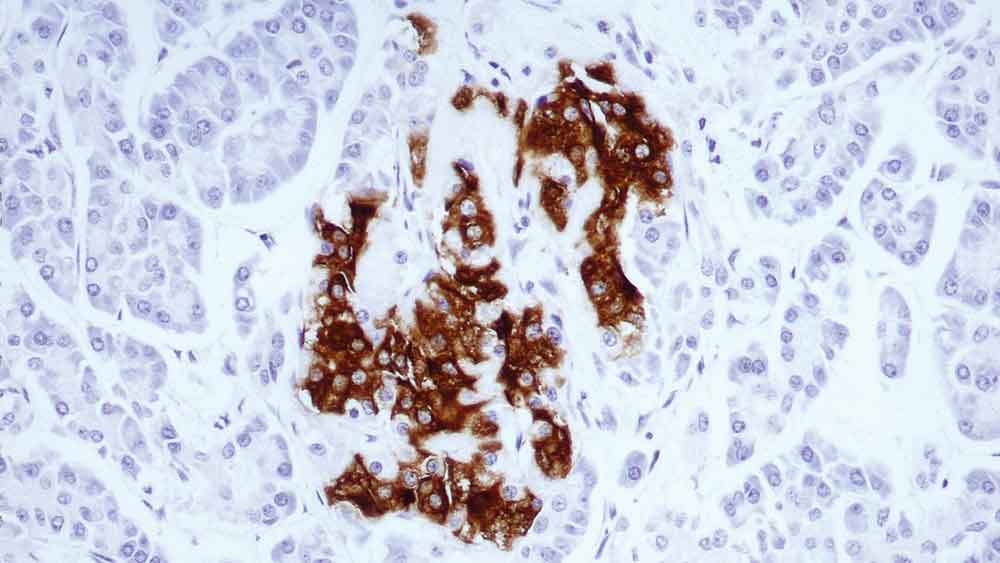

Human pancreas: immunohistochemical staining for insulin-containing cells. Note intense cytoplasmic staining. Insulin: clone 2D11-H5

Insulin is a hormone secreted by the beta cells of the islets of Langerhans in the pancreas. It promotes glycogen storage, formation of triglycerides, and synthesis of protein and nucleic acids. Reports of immunocytochemical investigation reveal the presence of insulin in the cytoplasm of certain islet tumors. However, in some instances insulin-positive granules are sparse and form a margin against the cell membrane.